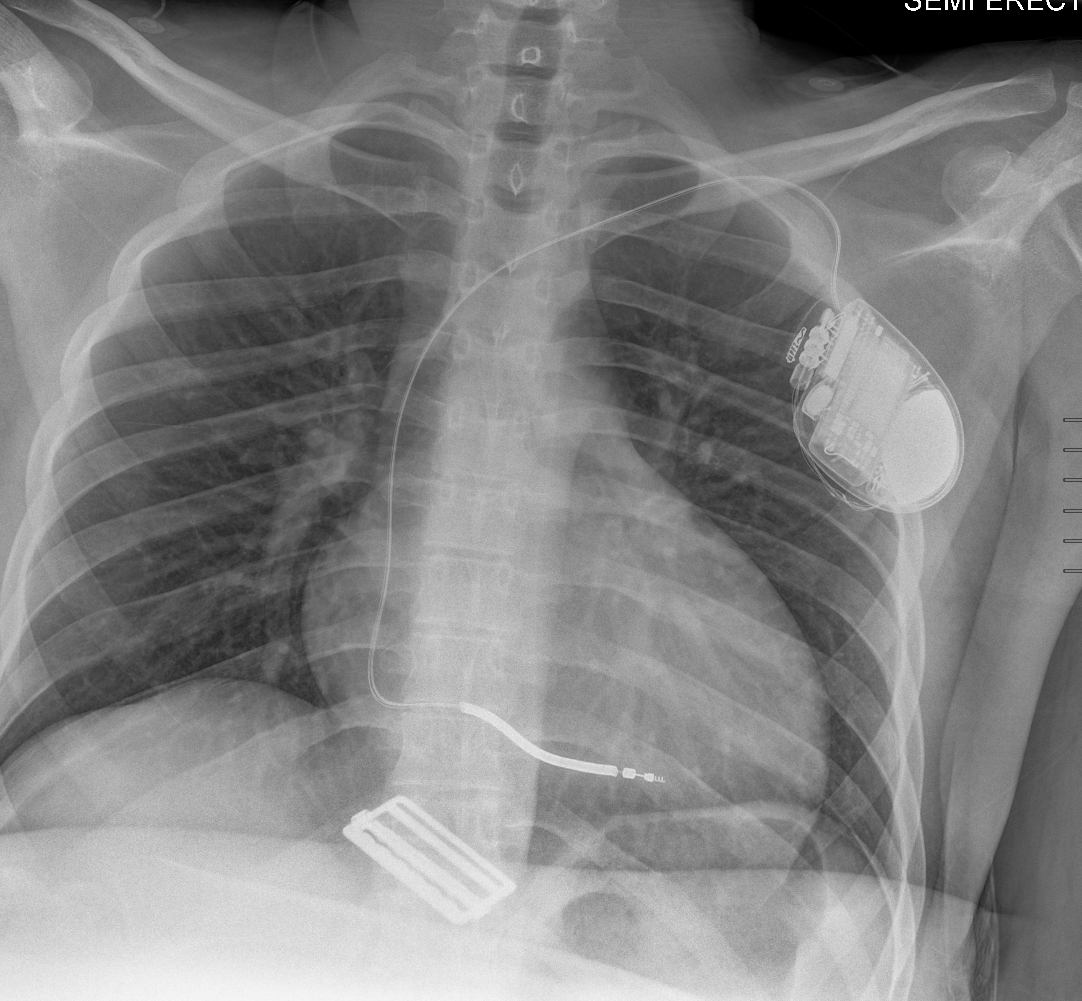

Findings

Soft Tissues

Bone

Joints and alignment

Other findings